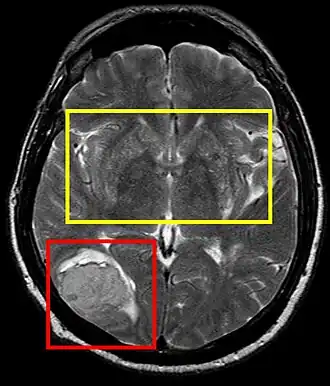

Sistema nervioso central

La hipertensión arterial persistente puede causar un accidente cerebrovascular trombótico o embólico, infartos lacunares o un accidente cerebrovascular hemorrágico con hematoma intracerebral, entre otros. Tanto la presión sistólica y diastólica elevadas son perjudiciales; una presión diastólica de más de 100 mmHg y una presión sistólica de más de 160 mmHg han dado lugar a una incidencia significativa de enfermedades cerebrovasculares. Otras manifestaciones de la hipertensión incluyen la encefalopatía hipertensiva, lesiones microvasculares cerebral y la demencia de origen vascular como consecuencia de múltiples infartos del sistema nervioso central.